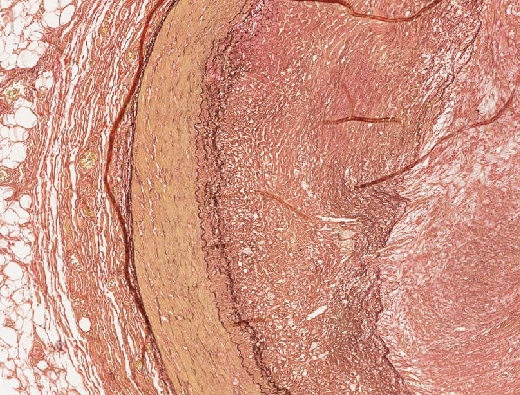

• Organdiagnose: Koronararterie

• Querschnitt einer Koronararterie mit arteriosklerotischer Plaque

• subtotale Stenose durch inkompletten thrombotischen Verschluss

• Thrombus: schon teilweise organisiert

Abb. 427: Geschichteter koronarieller Thrombus mit Rekanalisierung.